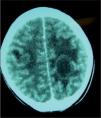

Se realiza tomografía computarizada (TC) cerebral, y se objetivan dos lesiones quísticas parenquimatosas en lóbulos parietales.

Se repite TC cerebral, apreciándose las dos lesiones quísticas previamente descritas, con aumento del edema vasogénico perilesional, por lo que se inicia tratamiento con dexametasona.

Se realiza resonancia magnética (RM) cerebral (figs. 1 y 2), en la que se visualizan hasta seis lesiones quísticas con cápsula hipointensa en secuencias potenciadas en T2, y con realce en anillo tras la administración de contraste, sugestivas de neurocisticercosis en fase coloidal.

Imagen de RM sagital que muestra las lesiones quísticas en sustancia blanca subcortical localizadas en lóbulos parietales, con fina cápsula hipointensa en T2, sugestivas de neurocisticercosis en fase coloidal. También se realiza espectroscopia de las lesiones, objetivándose gráfica patológica no tumoral.